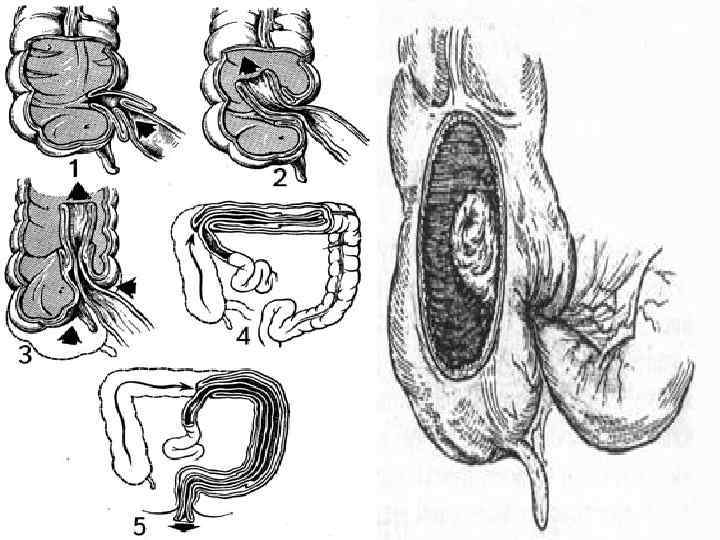

Илеустың жедел, созылмалы және ауыспалы түрлерін бөледі. Жедел илеус - ойда жоқта, бұған дейін дені сау адамда басталып, оның жағдайы тез ауырлайды. Созылмалы илеусқа бәсендеп өсетін ішек ісігі, ал ауыспалы түріне ішектің бұралуы үшыратады. Ішектің толық бітелуі немесе жартылай бітелуі мүмкін. Жартылай бітелуінде нәжіс және газ аздап шығады. Ішек түйілуінің барлық түрлерін механикалық және динамикалық деп екі топқа бөледі. Механикалық деп ішектің бұралуында, қысылуында, бітелуінде, сырттан басылуында байқалатын түрін атайды. Механикалық илеус - странгуляциялық және обтурациялық болып екіге бөлінеді. Странгуляциялық түрінде ішек сыртқы себептен түйіледі. Бұңда ішек ғана емес, оның шажырқайы қысылып қан айналысы бүзылады да қысылған ішектің некрозы басталады.

Странгуляцияға ішек бұралуы, байлануы, қысылуы, күрмелуі себеп болады. Обтурациялық түрінде ішек ісікпен, аскаридамен, дәкелі құрғатқыш (операцияда ұмытылған) бітеледі. Қан айналысы онша бұзылмайды. Өйткені шажырқай қысылмайды. Ішек түйілуінің келесі себебі инвагинация - ішекке ішек еніп оның бітелуіне қоса шажырқайдың қысылып, қан айналысы бұзылуы байқалатындығынан илеустің бұл түрінде обтурация және странгуляция қоса байқалады. Ішектің қабырғасының тегіс етінің әлсізденуіне байланысты кездесетін ішек түйілуі динамикалық деп аталады. Илеустің бұл түрін тырысқан және салды деп екіге бөледі. Спастикалық түрі - ішек қабырғасының тырысуынан оның өзегі тарылуымен байланысты болса, паралитикалық илеусте ішек созылған, өзегі кеңіген, оның тонусы - қозғалуы нашарланған.

г) Бұралу (volvulus) - ішек өзінің түбірінде айналып бұралады. Бұралу ішектің ең қозғалғыш бөліктерінде ащы ішек пен сигма ішегінде кездеседі. Кан айналысының тоқтауы және ішек түйілуі бұралу мөлшеріне байланысты. Ішектің 1800 бұралуы ішек түйілуіне әкелмейді. 270 -3800 бұралу ішекті және шажырқай қан тамырларын толық бітеп, тез арада ішек гангренасына әкеледі. д) Жабысқақтар және тыртықтар - ішектегі қабыну үрдісінен және операциядан соң пайда болады. е) Күрмелу (Nodus) - странгуляциялық ішек түйілуінің ең ауыр түрі. Күрмелу ащы ішек арасында, немесе ащы және тоқ ішек арасында пайда болады. Бұндай науқастар 12 сағат арасында өліп кетуі мүмкін. Бұл байланған, күрмелген ішектің шапшаң гангренаға шалдығуымен байланысты. Күрмелуге ішектің көп бөлімінің қатынасуы күшті экссудацияға, шокке соғады. Егер ішектің көп бөлшегі күрмелсе метеоризм шамалы. Ішек күрмелуіне ұшырағандардың өлімі 40 -50% жетеді.

. Ащы ішектің (заворот) айналуы . Ішектің ішекке енуі – (инвагинация).